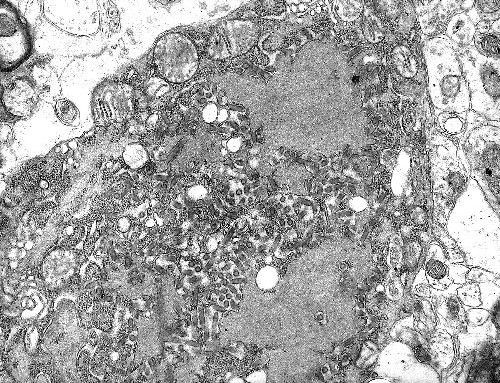

Virus SARS-CoV-2 cùng họ với virus SARS-CoV hay còn được biết tới là một trong các loại virus corona. Các trường hợp dương tính với SARS-CoV-2 đầu tiên được ghi nhận ở thành phố Vũ Hán, Trung Quốc. Virus này giống với SARS-CoV, có thể có nguồn gốc từ dơi, truyền qua một loài động vật trung gian trước khi lây nhiễm sang con người.

Kể từ khi xuất hiện, virus SARS-CoV-2 gây nên đại dịch Covid-19 đã khiến hơn 2,6 triệu người mắc bệnh và gần 185.000 người tử vong tính tới ngày 23/4, làm đảo lộn cuộc sống trên toàn thế giới.

Những người cao tuổi hoặc những người mắc các bệnh nền là những người có nguy cơ cao mắc Covid-19 nặng hoặc tử vong vì dịch bệnh này. Các triệu chứng thường thấy của bệnh nhân mắc Covid-19 là sốt, ho khan, khó thở và diễn biến thành viêm phổi ở một số trường hợp nghiêm trọng./.